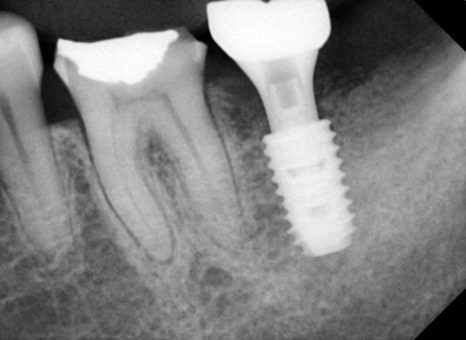

Implant surgery performed at the same time as extraction

In this case, the implant was placed immediately after the molar extraction.

✔ First implant surgery

✔ Guided bone regeneration performed

✔ Allograft bone graft performed in combination

The molar area often has insufficient bone,

so bone grafting is frequently performed together.